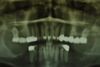

2. Extrem schlechte knöcherne Verhältnisse im Unterkieferseitenzahnbereich, die sich intraoperativ noch einmal als ungünstiger darstellten, als bereits in den Voruntersuchungen erkennbar.

3. Sehr dünne Implantate, die von ursprünglich zwei je Kieferhälfte auf letztendlich drei je Kieferhälfte umgeplant werden mussten.